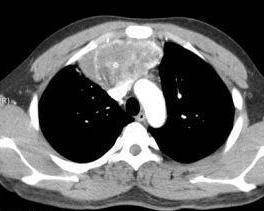

卵巢泡膜细胞瘤基本上是良性肿瘤。其有明显的内分泌功能,瘤细胞可以分泌雌激素,当黄素化或囊性变时,少数可有男性化功能。[1]